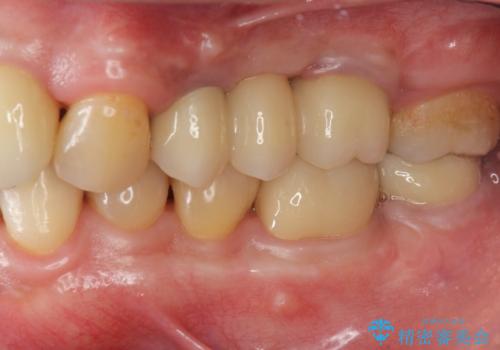

インプラント治療・セラミック治療を含む 全顎的虫歯治療

以上のような問題を、徹底的な虫歯治療、歯周外科、インプラント治療、部分矯正治療、精密根管治療を用いてひとつずつ解決ししっかりと長期的に食事を楽しめるような口腔内環境の再構築を目指します。